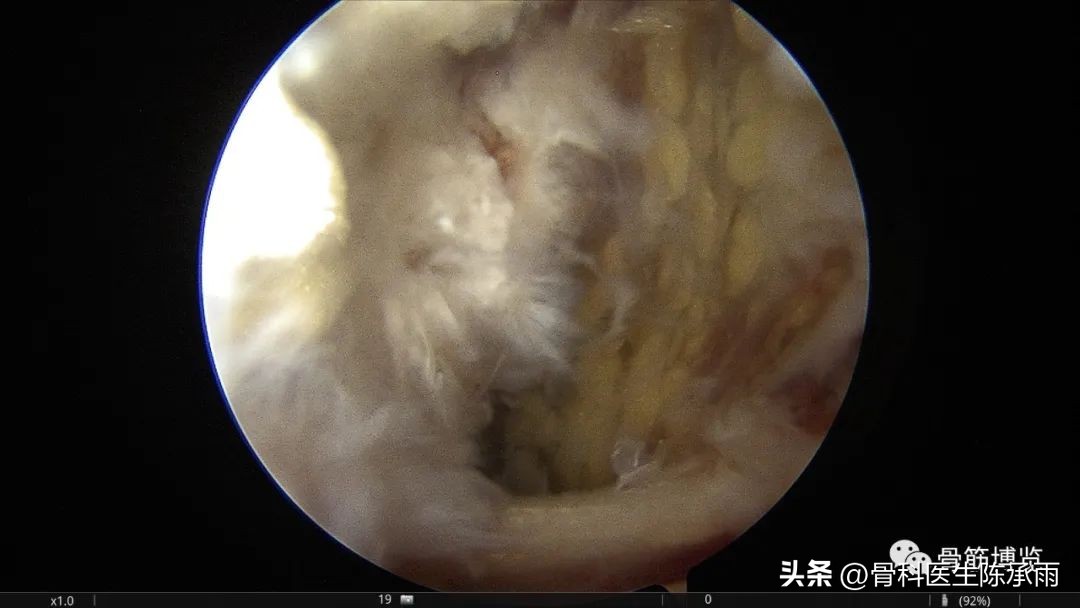

建立后侧内高位入路并刨开部分关节囊显露腓肠肌内内侧头

同时建立低位后内侧入路,于高位观察,低位操作,术前囊腔内注入少量美兰以便于术中镜下显露囊腔,充分扩大内口切除可见的囊腔内壁。

腓肠肌内侧头及半膜肌之间为囊肿内口,显露充分,囊肿内壁大部分切除

镜下囊肿切除∶镜头进入后间室,膝关节放置"4"字位,探针探查腘窝囊肿与关节腔的交通口,通常位于腘窝囊肿前方后内侧关节囊皱襞上。通过后内侧入路用刨削器将后内侧关节囊皱襞清除,充分地扩大腓肠肌内侧头与半膜肌之间的交通口,并清理增生的束带组织,使得腘窝囊肿和关节腔之间的滑囊液可以双向流动。充分显露腓肠肌内侧头,可于腓肠肌内侧头与半膜肌之间暴露出腘窝囊肿,通过关节镜对腘窝囊肿进行关节腔内引流。将刨削器和关节镜伸入囊肿内部清理囊腔,屈曲膝关节至"4"字位,从外侧挤压囊肿位置,从而使囊壁更易切除。也可以在手术前向腘窝囊肿内注射亚甲蓝 2ml,可在镜下更好显示囊肿,完全切除亚甲蓝染色的囊壁、囊内分割部分和可能的多发性囊肿的囊壁。

切除关节囊皱襞后,暴露出腓肠肌内侧头(箭头所示)在腓肠肌内侧头后内侧可暴露出腘窝囊肿(箭头所示)